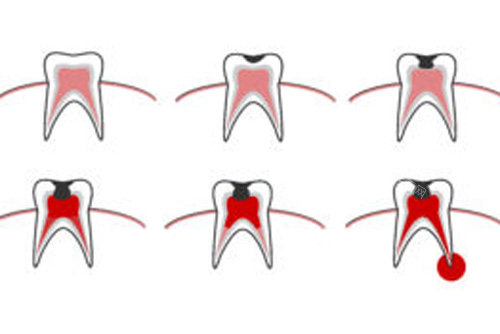

牙齿修复科:针对蛀牙、缺损等问题,提供全瓷冠、嵌体等修复方案,材料用的是德国威兰德全瓷,透光性接近真牙,补完牙基本看不出痕迹。